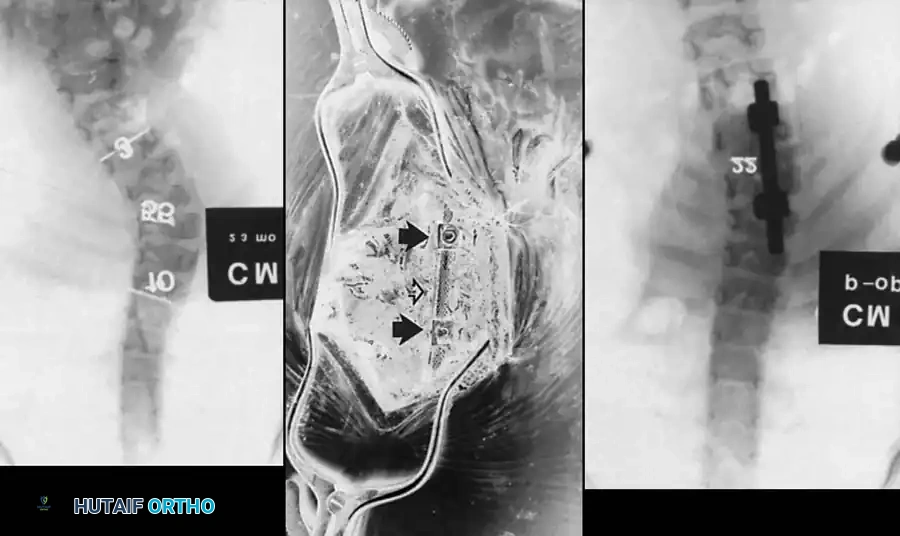

Image

Surgical planning and execution of complex congenital curve corrections.